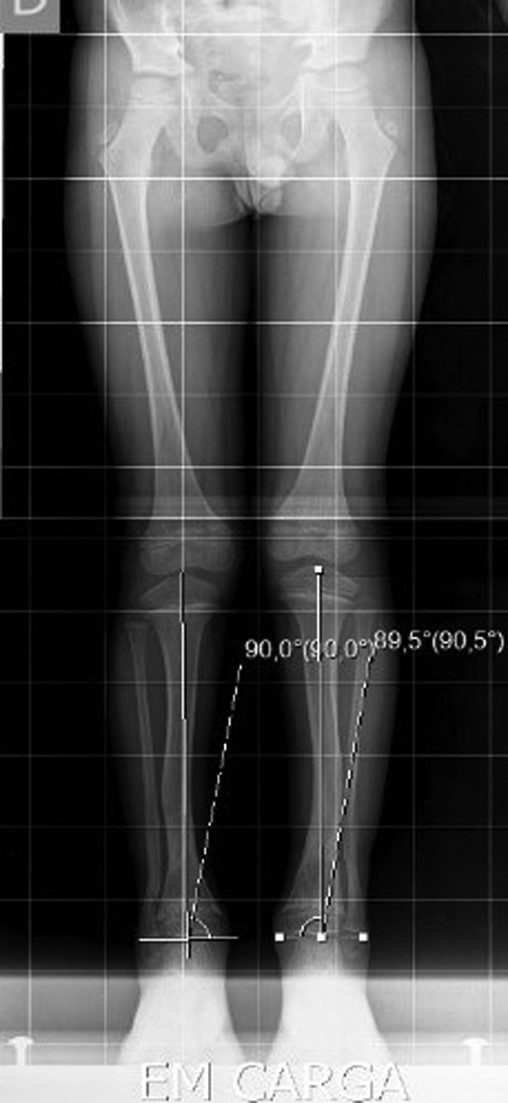

The X-ray showed a bowing of distal tibia, bilaterally, producing a varus deformity of 53 degrees (Fig. 2).